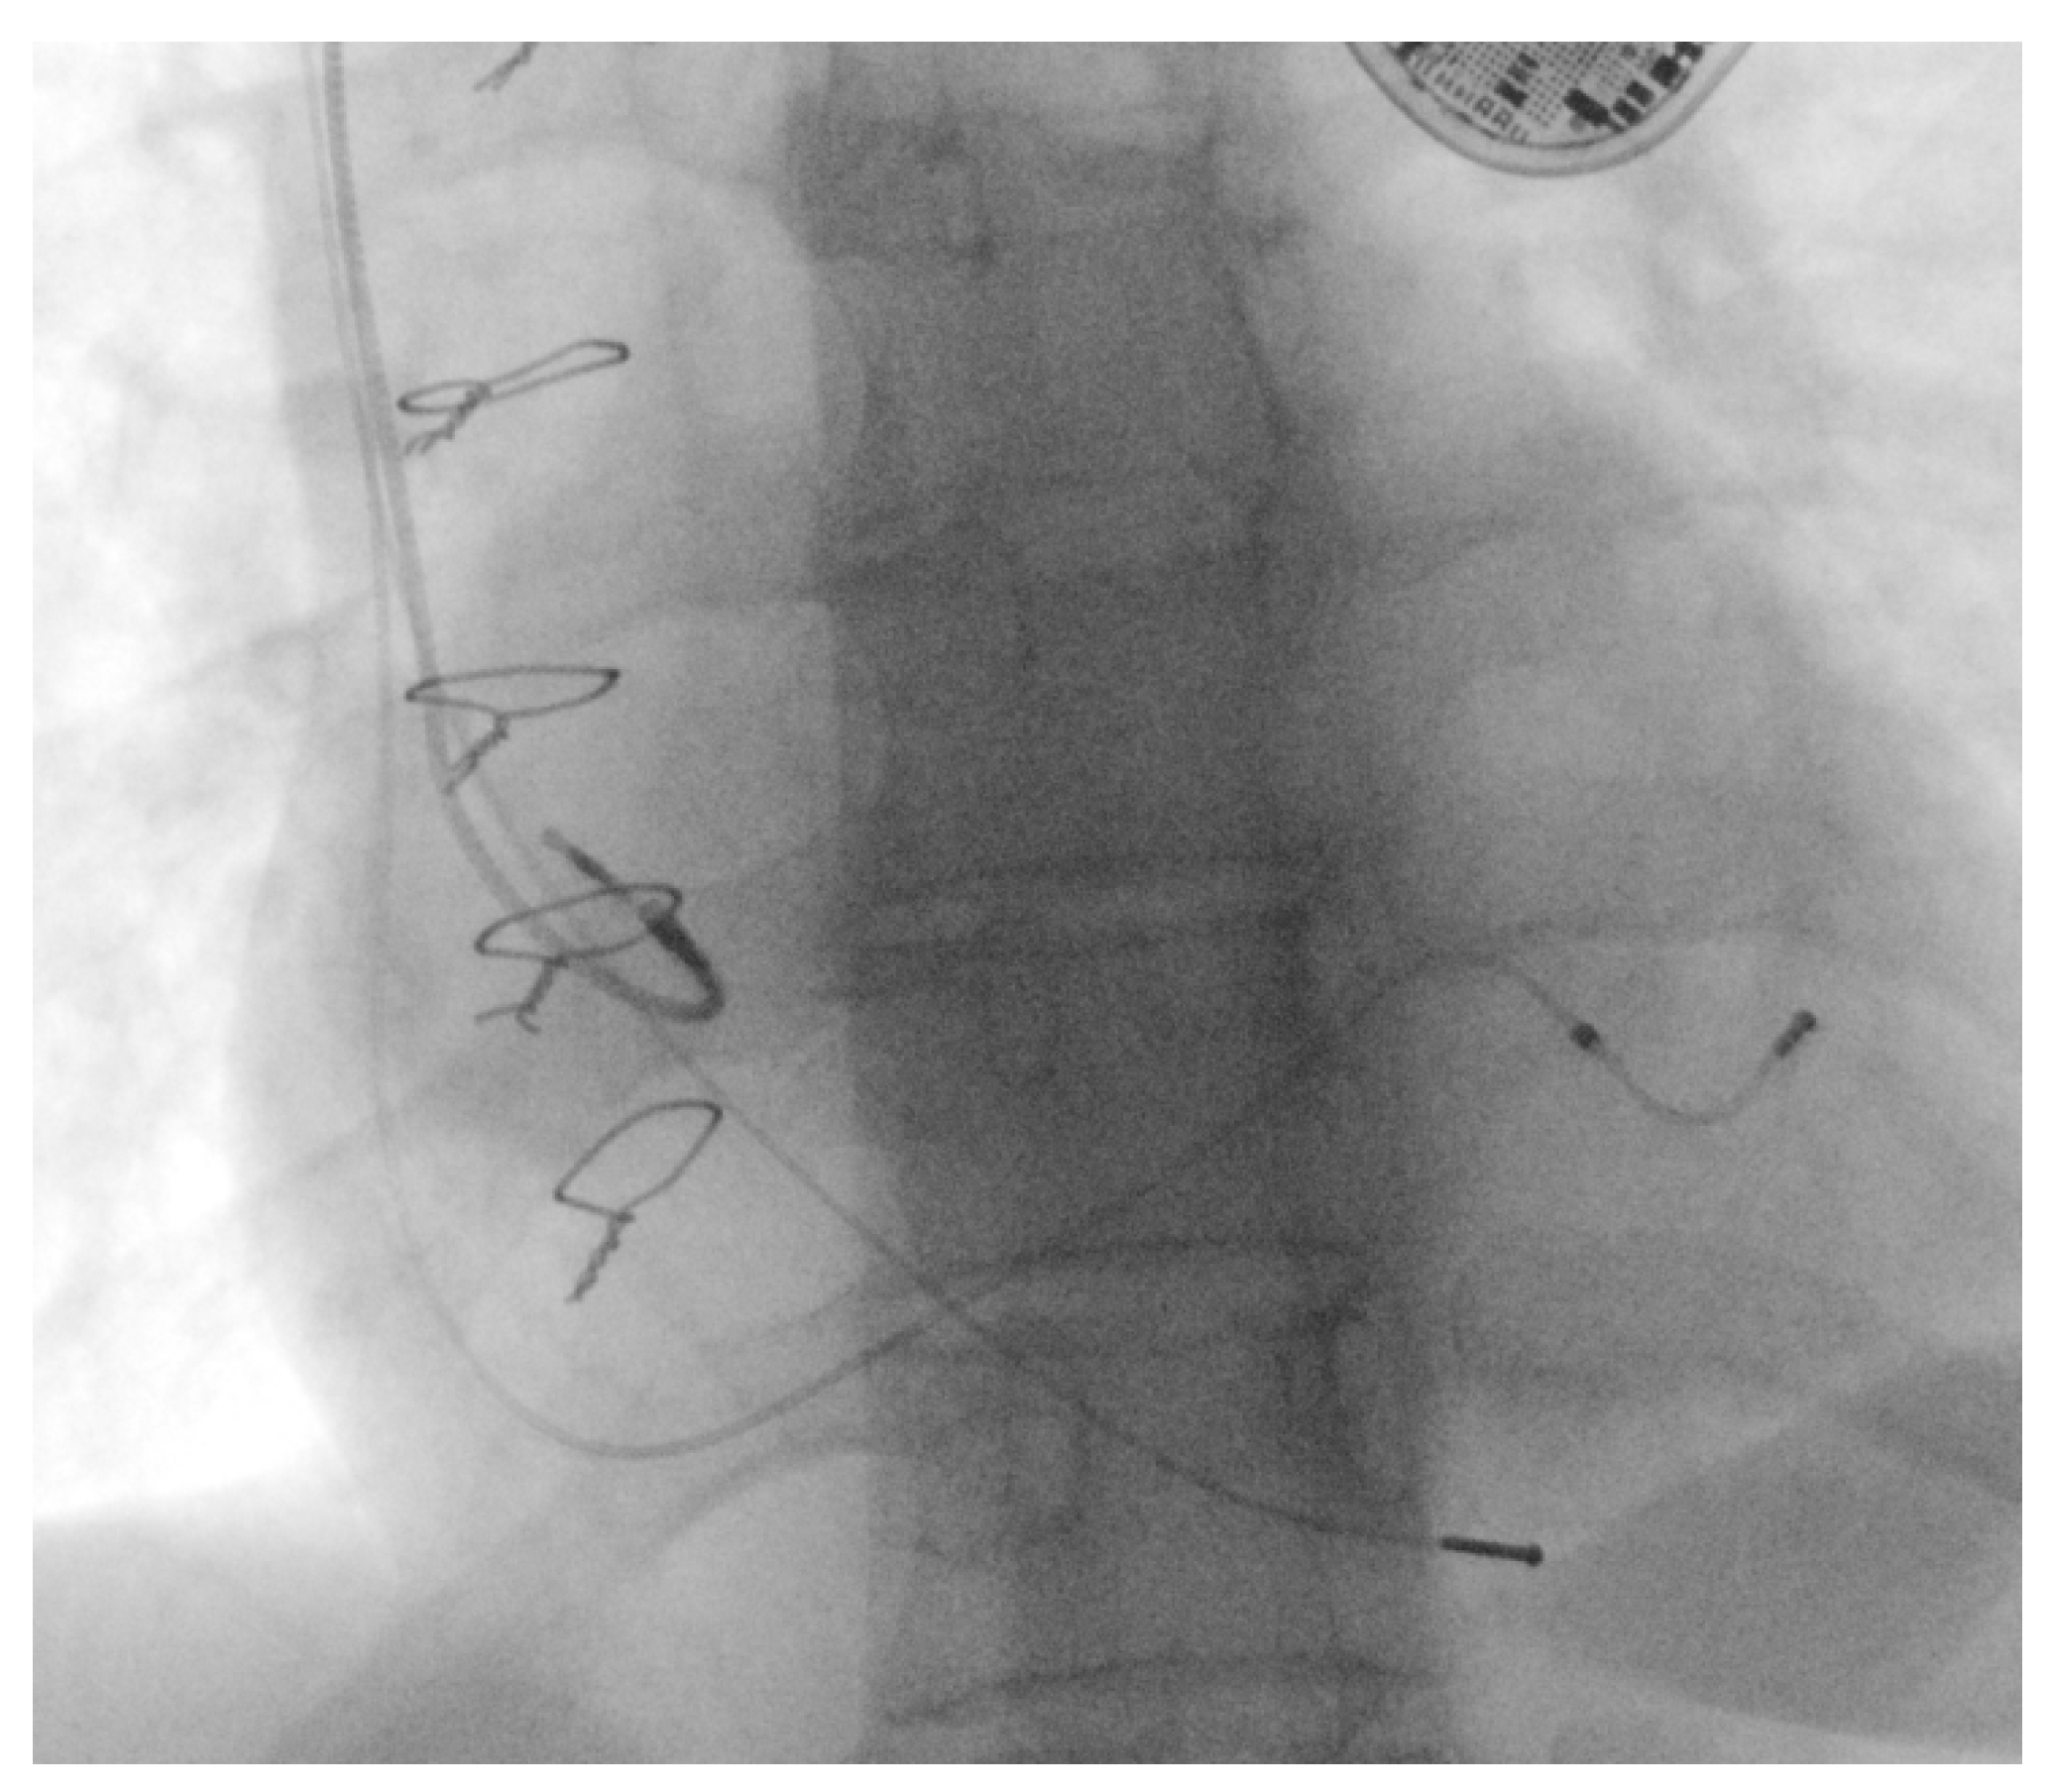

Iodinated contrast media was injected into the peripheral vein of the left arm, revealing occlusion of the left subclavian vein, with collateral circulation developed in the chest and neck and the suspicion of minimal circulation present on the deep subclavian venous axis (as shown in Figure 5).

Figure 5. Occlusion of the left subclavian vein, with collateral circulation.